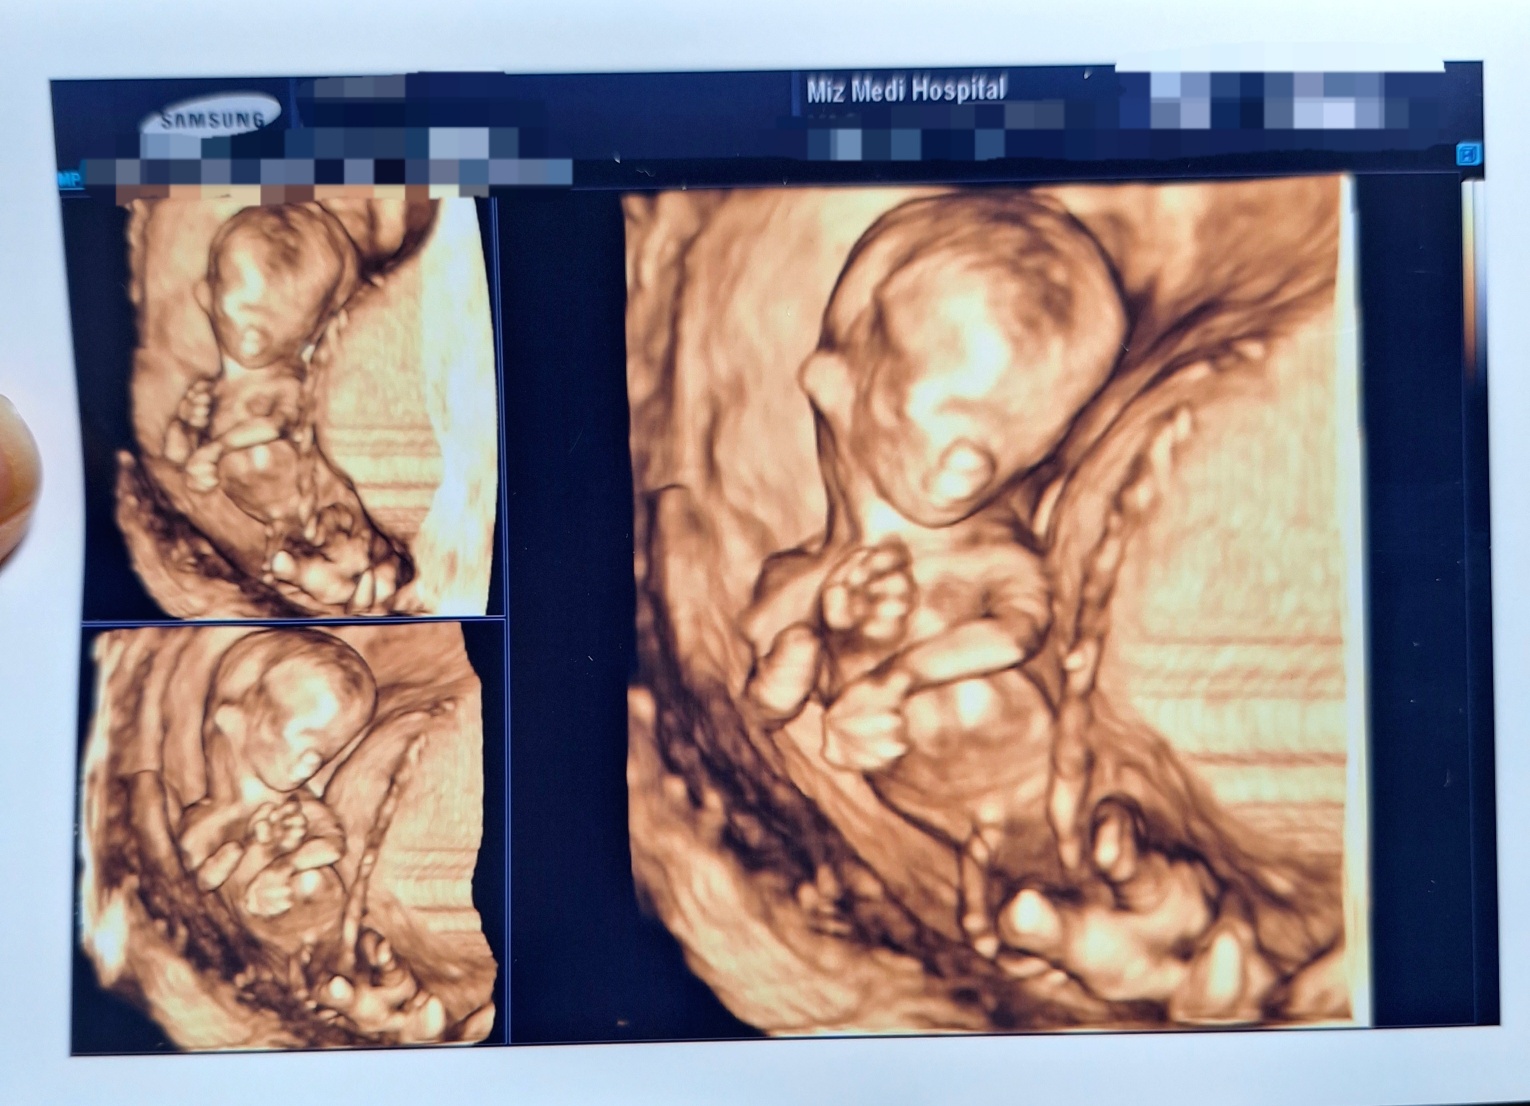

13주 된 엄지의 모습이예요! 와 한달만에 보았는데 어찌나 쑥쑥 컸던지 너무 놀라웠어요!

저번에 볼때는 마치 올챙이? 물고기처럼 팔다리가 너무 짧았는데, 지금은 팔다리가 너무 긴거 있죠!

그리고 엄지는 정말 쉴 새 없이 움직이더라구요 ^^; 선생님께서 오전 이른 아침 초음파 보는데도 정말 쉴새 없이 바쁘게 움직인다며 ㅎㅎ

마지막 사진처럼 다리를 쭉 뻗고 팔도 휘드로고 얼굴을 가렸다 폈다 하더라구요~

오래도록 계속 초음파를 보니 힘들었는지 첫번째 사진처럼 얼굴을 숨겨버렸어요! ㅋㅋ 즉각적인 반응이 얼마나 귀엽던지~

아직 눈 코 입 형상이 명확하진 않아서 누굴 닮았는지 (?) 잘 알아볼 순 없지만~ 너무너무 신기하네요!